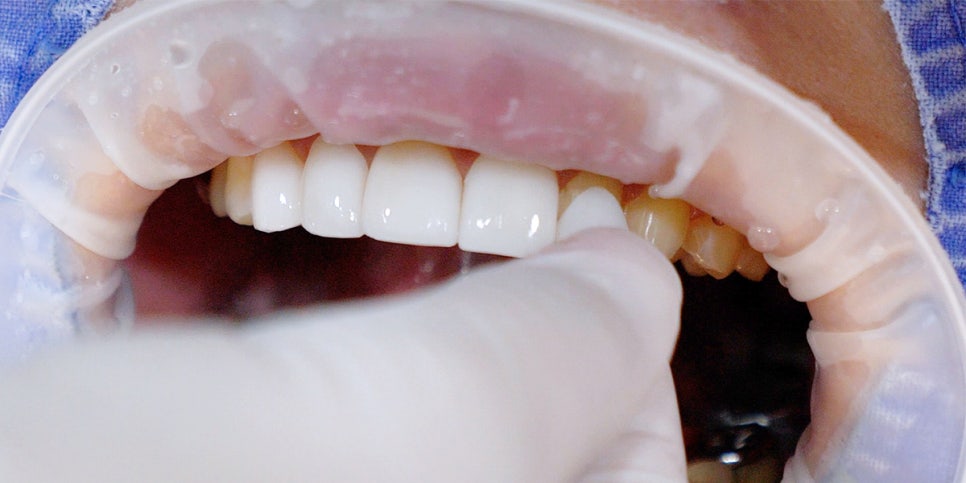

미니쉬의 다양한 형태

미니쉬는 치아 상태에 따라 다르지만 0.1mm까지 얇게 가공돼요.

그래서 붙이기 전 미니쉬만 보면 불안해 보일 수 있죠.

하지만 치아와 결합하면 완전히 한 덩어리가 되면서 전체 두께로 보면 충분히 두꺼워져요.

미니쉬 접착

종이를 예로 들어볼까요?

한 장은 쉽게 찢어지죠.

그런데 종이 100장을 접착제로 단단히 붙여 놓으면?

하나의 두꺼운 덩어리가 되어 쉽게 찢어지지 않아요.

미니쉬도 비슷한 원리예요.

치아와 화학적으로 결합해 원래 치아처럼 두께가 회복되기 때문에 쉽게 깨지지 않는 거죠.